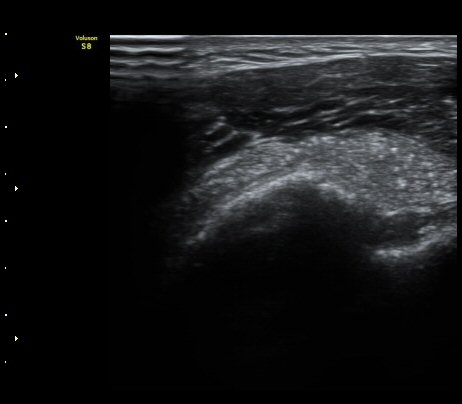

À̵ιڱ٠Ⱦ´Ü¸é°Ë»ç¿¡¼­ Á¡¾×³¶³» °í¿¡ÄÚ ¼®È¸È­ À½¿µµéÀÌ °üÂûµÊ(±×¸² 1, 2, 5)

¿ÜȸÀüÀÇ Á¦ÇÑÀ¸·Î °ß°©ÇϱٰÇÀÌ ¼öÆòÀ¸·Î °üÂûµÇÁö ¸øÇϰí À̵ιڱ٠ǥÃþ¿¡

¼®È¸È­ À½¿µÀÌ °üÂûµÊ(±×¸² 3)

À̵ιڱ٠Á¾´Ü¸é°Ë»ç¿¡¼­µµ Á¡¾×³¶³» ¼®È­È­ À½¿µÀÌ °üÂûµÊ(±×¸² 4).